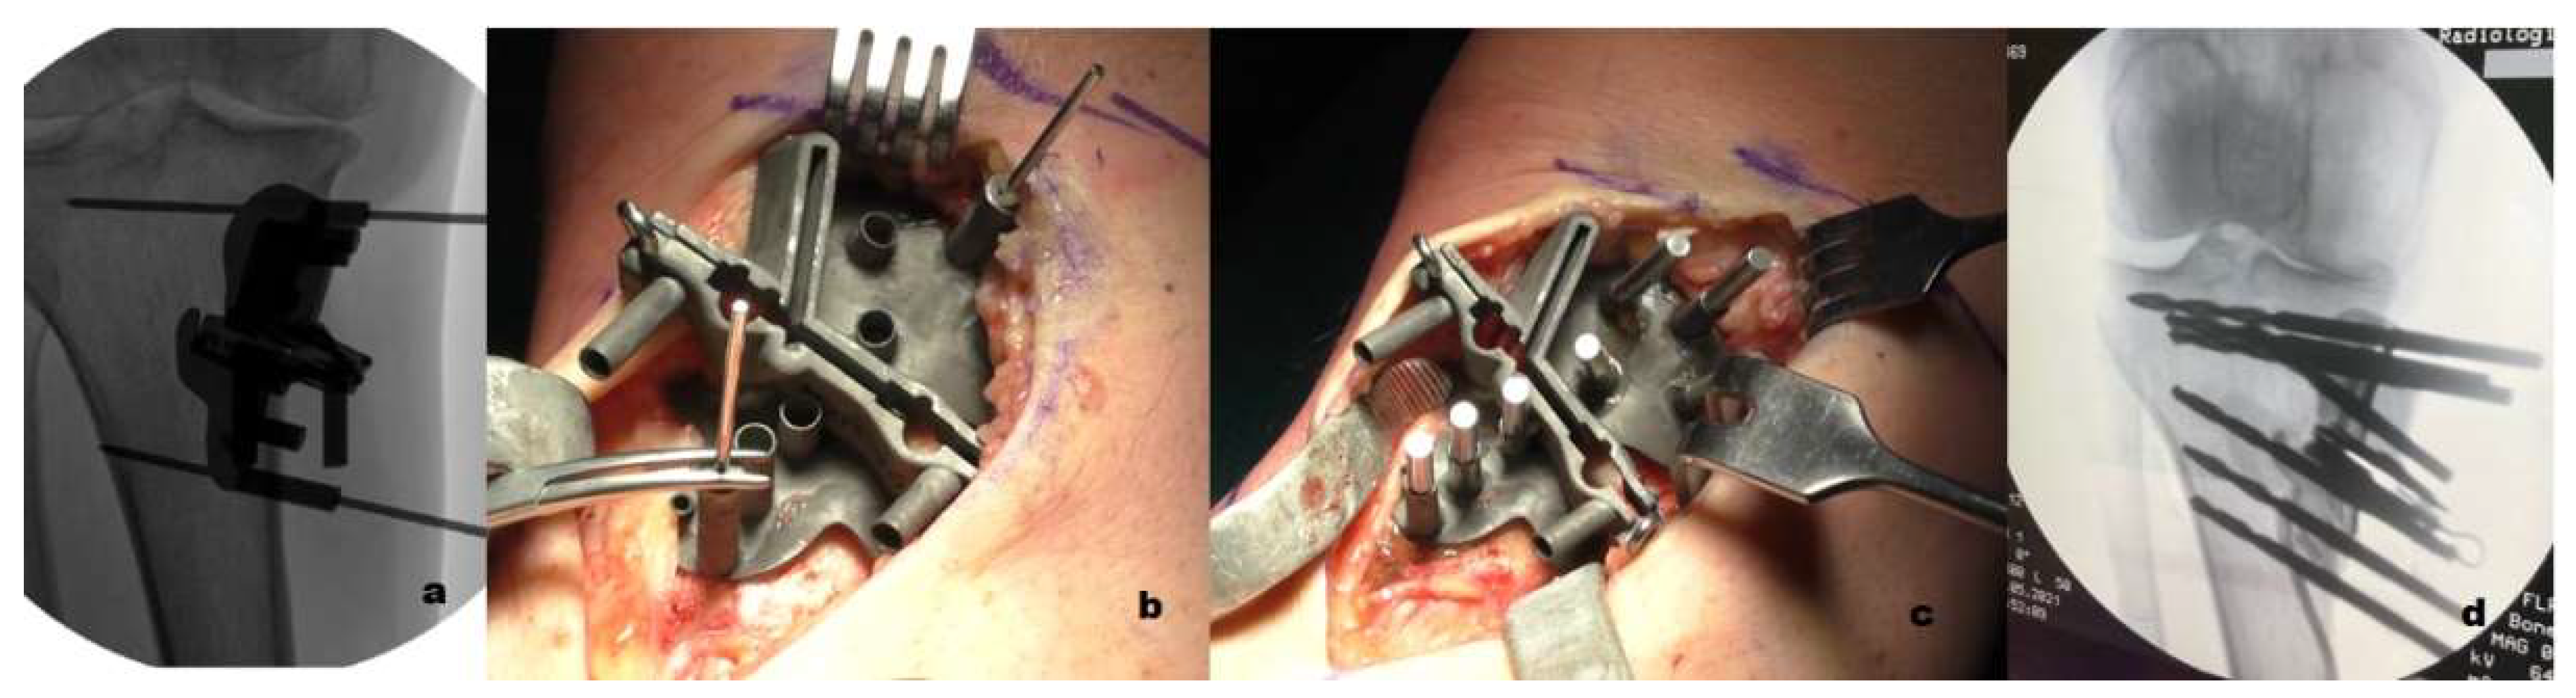

4.3. Surgical Technique